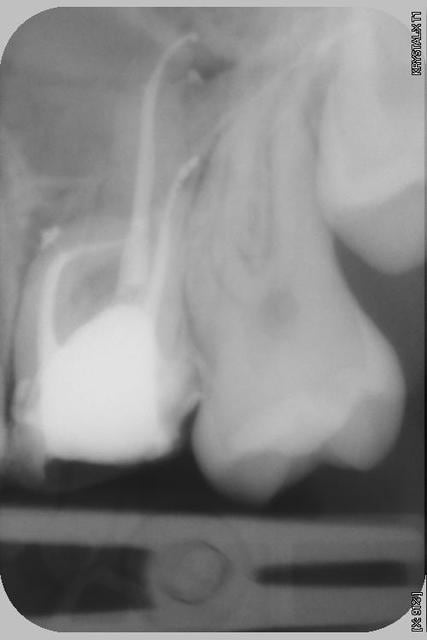

Le plan de traitement peu sembler étonnant, d'aucun me demanderons pourquoi pas extraction implant? Il ce trouve qu'il s'agit d'une très jeune patiente (16ans), "bénéficiant" de la couverture maladie universelle, mais pas de moyen financiers...donc plutôt que de l'édenter pour lui apprendre... je traite.

D'ou mon envie de au moins vous montrer cette radio, qui n'avait strictement aucun intérêt ni pour elle ni pour sa mère, qui sont par ailleurs toutes les deux très gentilles.

Bravo. Et comme bogenom, je suis impatient ce connaître ton protocole (je suis toujours admiratif devant les radios avec canaux latéraux obturés)

Bon je m’y colle.

Reconstitution au verre iono (fujifast c’est le9 je crois)

Digue

Ouverture sous microscope, ainsi que travail dans les chambres et sur les premiers tiers.

Détermination de la LT, ici ca ne se voit pas mais c’est le distal delà 26 qui m’a pris le plus de temps, tous les canaux avaient une courbure apicale, bilan quelques limes de 006, un gros paquet de 008 et de 010 a la poubelle mais tous sont perméables.

J’utilise les protaper SX, S1car je n’ose pas faire descendre le SX, puis S2 (s2 manuel sur le distal de la 26 toujours lui, le rotatifs s1 sortant despiralé alors qu’il était neuf…ouf !)

Puis F1 et F2 en manuel.

Hypochlorite 1 a 2 ml entre chaque instrument, plus passage d’une 008 ou 006 entre chaque instruments ou tout du moins au début, et re hypochlorite.J'aila certitude que c'est a ce moment que les lateraux ce nettoient.

A la fin 2mn d’EDTA liquide, puis ici 5 mn d’hypochlorite, j’aurais préfère 10…mais bon le temps…ici aussi ca aide bien pour les lateraux ;) j'utilise un chronometre pour etres sur de rincer assez longtemps.

Obturation au thermafil, j’utilise plus facilement le e-fil qui ressemble au sytemeB, pour chauffer ma gutta, mais encore une fois…le temps, mais aussi la certitude de ne pas descendre assez notamment dans le mv de la 26 m’ont fait choisir le termafil.

Pour finir pas de mv2 a proprement parler, je m’explique, au début j’étais certain qu’il était là, j’étais bien content(chui maso) je l’instrumente souvent en dernier, lorsque le mv1 est nickel, et surtout que le bain d’hypochlorite m’ai donné un peu plus de visibilité, (sous microscope c’est flagrant) et ici en fait le mv2 ressemblé plus a un isthme descendant le long du mv1, je l’ai nettoyer avec le SX et avec l’aide de l’EDTA pour le vider des débris.

Début des opérations, 9h30, fin 11h15 a noter que le RDV était a 9h mais j’étais déjà en retard.